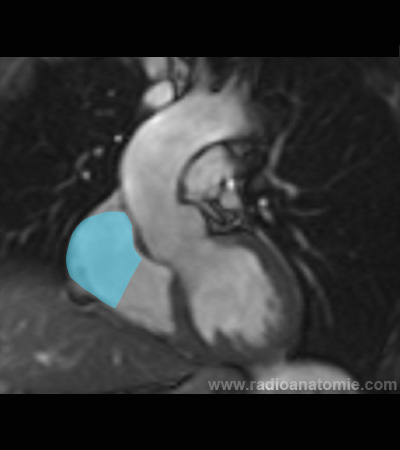

Chambre de chasse du ventricule gauche LVOT2

Plan valve aortique

Plan chambre de chasse du ventricule gauche (LVOT)

Valve aortique

Muscles papillaires

Ventricule gauche

Ventricule droit

Oreillette droite

Aorte ascendante

Artère pulmonaire

Septum interventriculaire